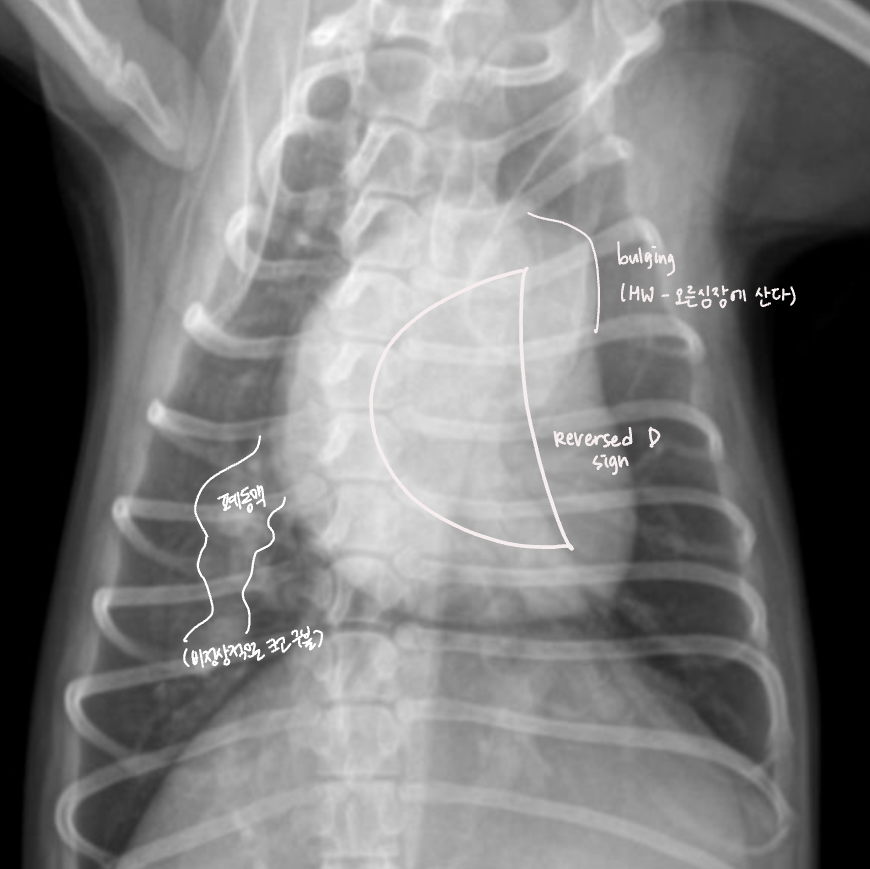

4. Pleural Space

| Pleural effusion (ํ์) | Pneumothorax (๊ธฐํ) | |

| ํ๊ฐ(pleural cavity)์ ๋ฌผ์ด ์ฐฌ ๊ฒ (ํ์ ์ฐจ๋ฉด โ ํ์์ข ) | ํ๊ฐ์ ๊ณต๊ธฐ๊ฐ ์ฐฌ ๊ฒ (ํ์ ์ฐจ๋ฉด โ ํ๊ธฐ์ข ) | |

| Radiographic signs interlobar fissure ๋๊ป๊ฒ ๊ด์ฐฐ๋๊ณ , ํ๋ฒฝ์ด ๋จ์ด์ ธ ๋๊ฐ ๊ฒ์ฒ๋ผ ๋ณด์ | Radiographic signs ์ฌ์ฅ์ด ๋ ์๊ณ , ํ๊ฐ ์ชผ๊ทธ๋ผ๋ฆ | |

| - Interlobar fissure widening - Lung retraction - Pleural wall thickening - Scallop sign - Cardiac effacement - Blunt angle | - Retraction of pleural surface - Collapsed lung (โ opacity ์ฆ๊ฐ) | |

![]() | ![]() | |

![]() ![]() | ![]() ![]() | |